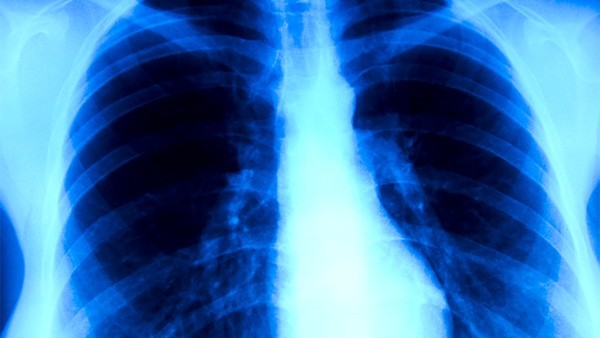

肺心病是大家常见的一种肺部kaiyun全站网页版登陆,肺心病已经严重影响了患者的生活质量,随着医学的发达,治疗肺心病的方法有很多种,肺心病患者可以选择西药、中药或者是中成药,那么,肺心病用什么药好呢?

由于绝大多数肺心病是慢性支气管炎、支气管哮喘并发肺气肿的后果,因此积极防治这些kaiyun全站网页版登陆是避免肺心病发生的根本措施。应讲究卫生、戒烟和增强体质,提高全身抵抗力,减少感冒和各种呼吸道kaiyun全站网页版登陆的发生。对已发生肺心病的患者,应针对缓解期和急性期分别加以处理。呼吸道感染是发生呼吸衰竭的常见诱因,故需要积极予以控制。